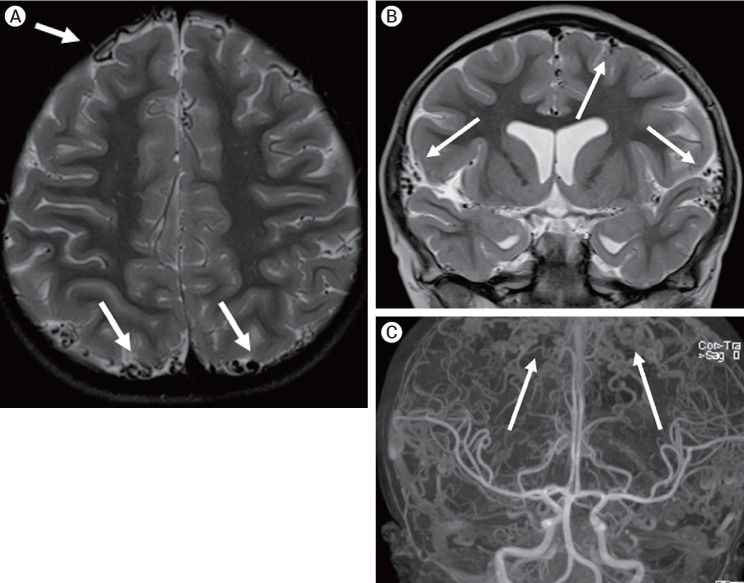

Partial trisomy of the long arm of chromosome 17 (17q) is a rare but clinically recognized syndrome that involves facial dysmorphisms, skeletal abnormalities, and global developmental delay, as well as various reports of cardiovascular, renal, and central nervous system abnormalities. This report presents a novel neuroradiologic finding of diffuse enlarged, tortuous cortical veins with physiological antegrade flow in a child with a microduplication of the distal end of 17q. To our knowledge, this finding has not been described previously. Although the exact cause for the cortical vascular anomaly is currently unknown, this duplicated region contains genes of interest for future studies that focus on normal and abnormal angiogenesis.